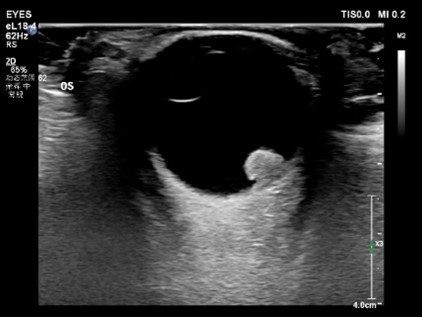

超声检查不仅能够直观的观察眼部病变形态结构,更是目前唯一能够反应眼部血管血流动力学的影像学检查方法。然而由于眼部血管分布密集表浅,普通超声检查的分辨力和敏感性无法满足精准诊断的临床需求。超微血流成像技术是一种新型的可以检测出高分辨率和最小伪影的小血管血流的检测方法,可以用于检测组织中缓慢和微弱的血流解剖。但对于视网膜动静脉栓塞,高血压、糖尿病等视网膜病变,肿瘤病变良恶性鉴别等仍存在不足。近年来随着超声造影技术的迅速发展,超声造影技术对微小血管和低流速、低流量血流信号具有更高的检出率,并且能更优质的显示组织血流的灌注特点。超声造影其独特的显像特点将在眼部占位,眼部血管性病变中取得更大的发展。将超声造影联合超微血流成像技术应用于眼底病变的观察可能为眼科疾病的诊断和鉴别诊断提供一种创新的融合显像检查方法。